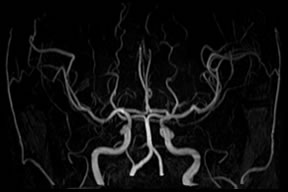

内臓動脈瘤への経皮的塞栓術

脾門部の動脈瘤に対して塞栓用コイルにて塞栓術を施行しています。